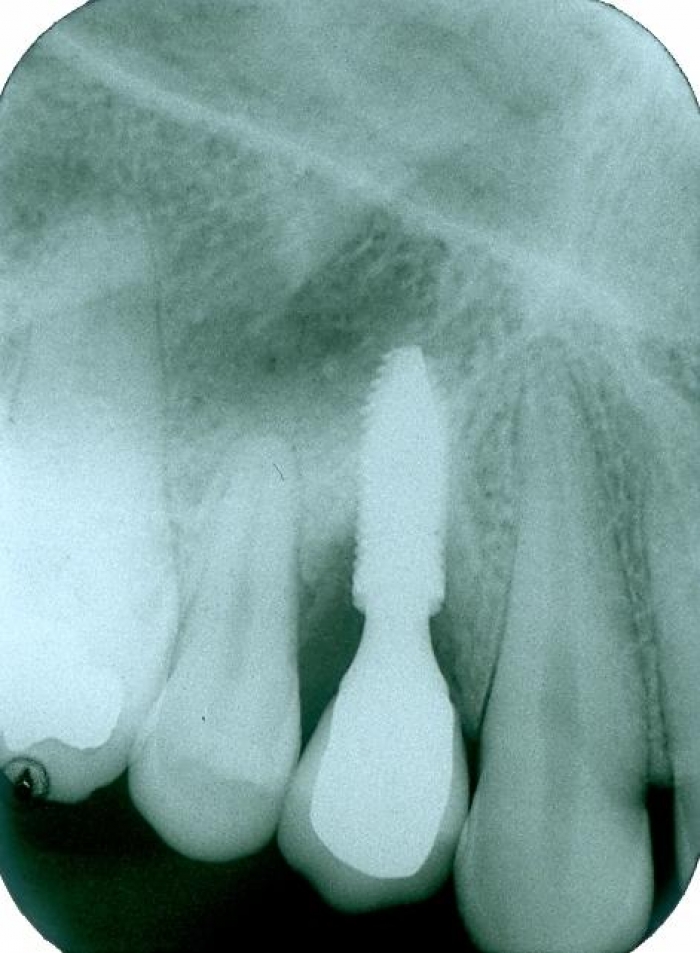

Raio X do implante Cone Morse